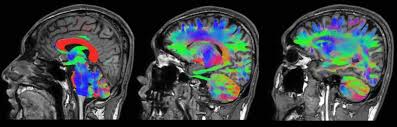

- Elke kleur in het plaatje is een ander deel van het brein met een eigen min of meer afgebakende functie.

- Door hierop in te tunen kunnen we achter de verstoringen komen.

Het Human Connectome Project (HCP) is een van de grootste wetenschappelijke uitdagingen van de 21e eeuw aangegaan: het in kaart brengen van de menselijke hersenen, met als doel de structuur ervan te koppelen aan functie en gedrag.

Ons brein heeft een unieke frequentie. Deze frequenties kunnen met een MRI zichtbaar gemaakt worden.

In het Human Connectome Project worden bij proefpersonen in fMRI metingen gedaan terwijl ze een functie uitvoeren. Zo zijn er al vele breinnetwerken gedetecteerd.